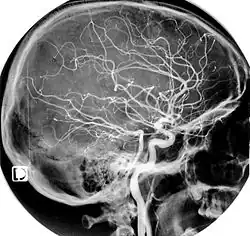

L'artère carotide interne (aussi appelée carotide interne droite ou CID) est une artère issue de l'artère carotide commune, de la branche externe plus précisément, et vascularisant la plus grande partie du cerveau, l'oreille interne et l'œil.

Elle pénètre dans la boîte crânienne par le canal carotidien situé dans le rocher (base du crâne) de l'os temporal selon un trajet vertical rétro styloïdien. Puis, dans son trajet pétreux, au niveau du foramen déchiré, elle donne dans le crâne une première branche collatérale qui est l'artère carotico-tympanique. En suivant, elle va transpercer le sinus caverneux, sortir par son toit et donner les dernières branches collatérales qui naissent près de la terminaison ; nous retrouvons l'artère cérébrale antérieure qui donnera l'artère hypophysaire supérieure ainsi que l'artère ophtalmique. De plus, dans cette région cérébrale, l'artère carotide interne va s'anastomoser avec l'artère cérébrale postérieure (dérivant de l'artère vertébrale) pour donner l'artère cérébrale moyenne du polygone de Willis.

L'artère carotide interne et ses branches contribuent à la formation du polygone de Willis, anastomose avec les artères homologues (du côté opposé) et celles issues de l'artère basilaire.